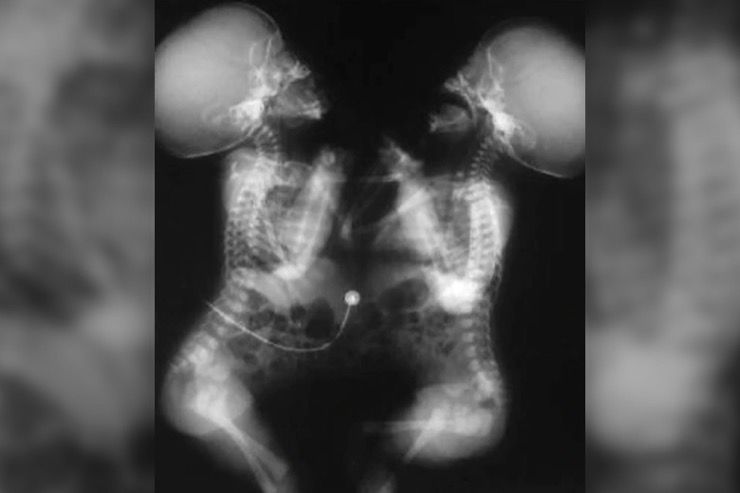

Australian Hospital Gives Conjoined Bhutanese Twins New Lease On Life